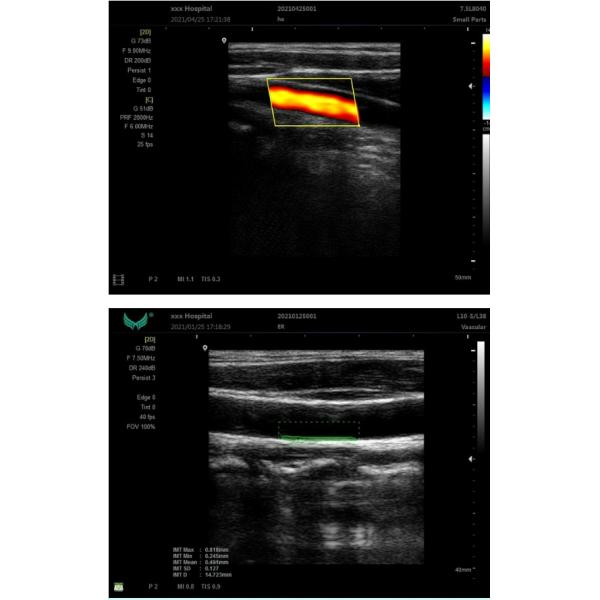

Imaging mode B,B+B,4B ,B+M,PW ;CFM

IMT automatic measure function;

| Main Parameter | Display modes: B, B/B,4B,B+M,CFM,B+CFM,PDI,B+PDI,PW; |

| THI imaging technology; | |

| IMT automatic measurement and display results; | |